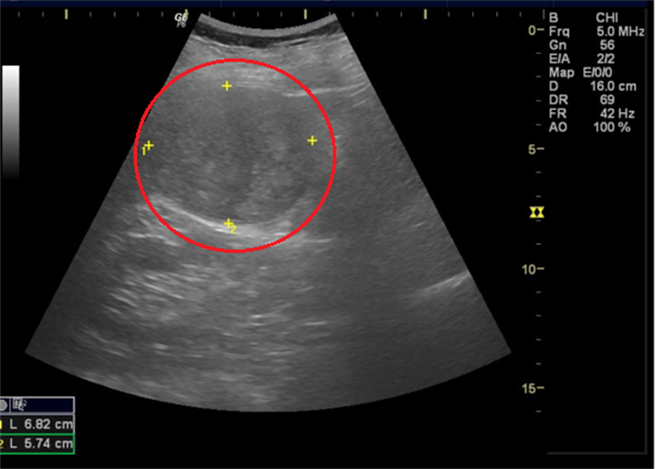

真是太幸运,做个体检竟发现肝臟有7公分大的肿瘤!一名69岁陈姓妇人日前体检抽血报告显示C肝病毒量和肝癌指数都偏高,超音波检查时发现肝臟右叶有约7公分大的肿瘤,至长安医院肝胆肠胃科就诊,进一步安排电脑断层确诊为肝细胞癌。所幸癌细胞并未扩散,病患在接受12周口服抗C肝药物后,手术切除肿瘤及部分肝叶,术后恢復状况良好,目前追踪6个月并无復发之情况。

许钰铨表示,该名妇人从不知道自己患有C肝,且身体状况并无任何不适,得知时心情非常错愕。幸好癌细胞并未扩散至血管或其他器官,因此先开立C肝全口服抗病毒药物,再安排手术切除肿瘤,追踪检查状况良好。